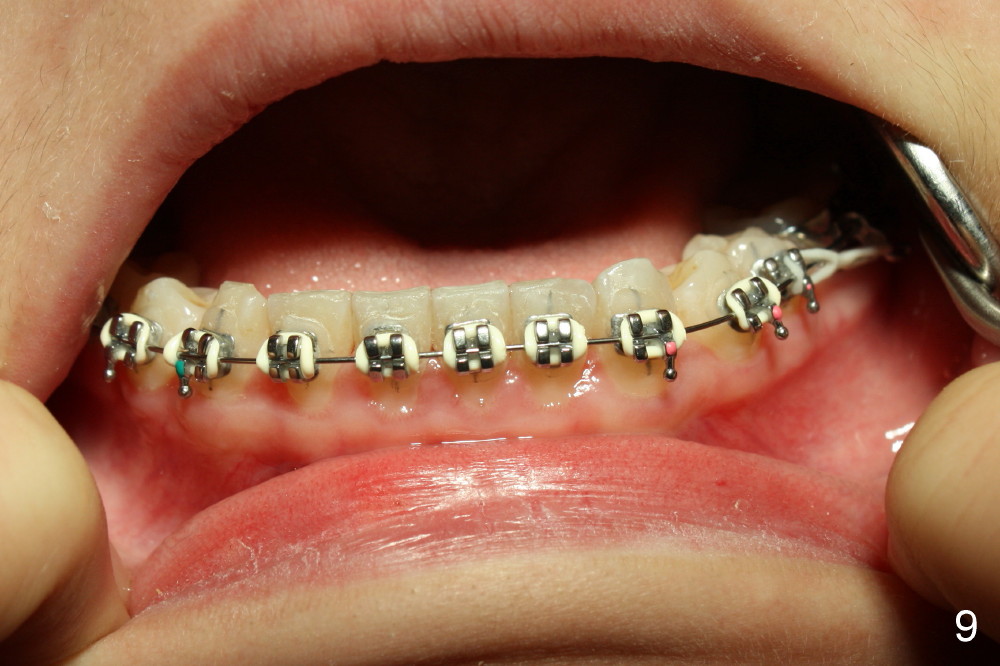

Ms. Xu, 16 years old, has bilateral posterior and UL 2 cross bite (Fig.1,2). L5s rotate (Fig.1-3: black lines).

The rotation of LL5 is so severe that the bracket is forced to be placed distal to the height of contour due to interference of LL4 (Fig.4). Because of delayed eruption of L3s (Fig.5: 3), the first niti wires (.014") are bent the most around them. Power chain x2 are placed between L5 and 6 (Fig.6) to correct the rotation of the former in timely manner.

In one month, wires (.016 niti just installed) are straighter although there is slight open bite on the left (Fig.7, compare to Fig.5). It may be beneficial to ask the patient to use (next appointment) an elastic between L3,4s to reduce the open bite. Power chains are continuously used bilaterally between L5,6 (Fig.7,8).